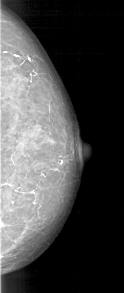

A_1191_1.LEFT_MLO

LEFT_CC LINES 5071 PIXELS_PER_LINE 2356 BITS_PER_PIXEL 12 RESOLUTION 43.5 OVERLAY

LEFT_MLO LINES 5491 PIXELS_PER_LINE 2476 BITS_PER_PIXEL 12 RESOLUTION 43.5 OVERLAY